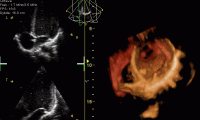

Exámenes de ultrasonido sobre el estado de salud de una persona.

© Public Domain, Kjetil Lenes, Wikipedia

A partir de los 50, o antes si tiene problemas de salud, se recomienda un examen médico rutinario. Para comparar, hágalo también antes del cambio. ¡Es SU vida!